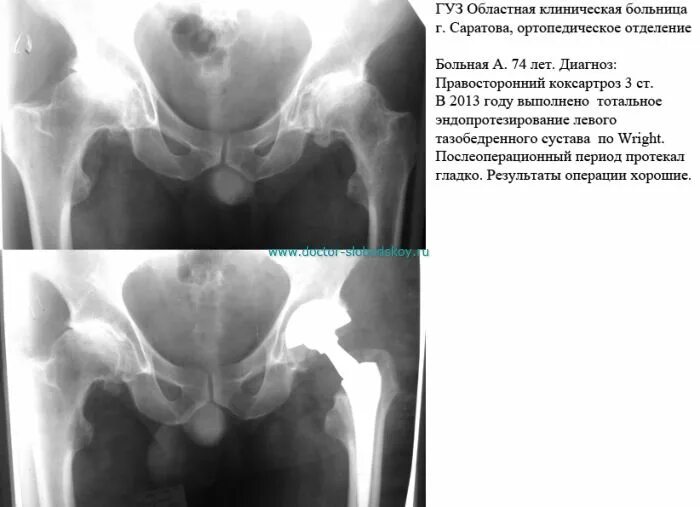

Почему после операции тазобедренного сустава